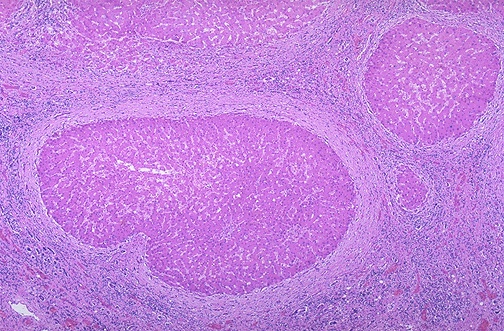

| Microscopically with cirrhosis, the regenerative nodules of hepatocytes are surrounded by fibrous connective tissue that bridges between portal tracts. Within this collagenous tissue are scattered lymphocytes as well as a proliferation of bile ducts. |